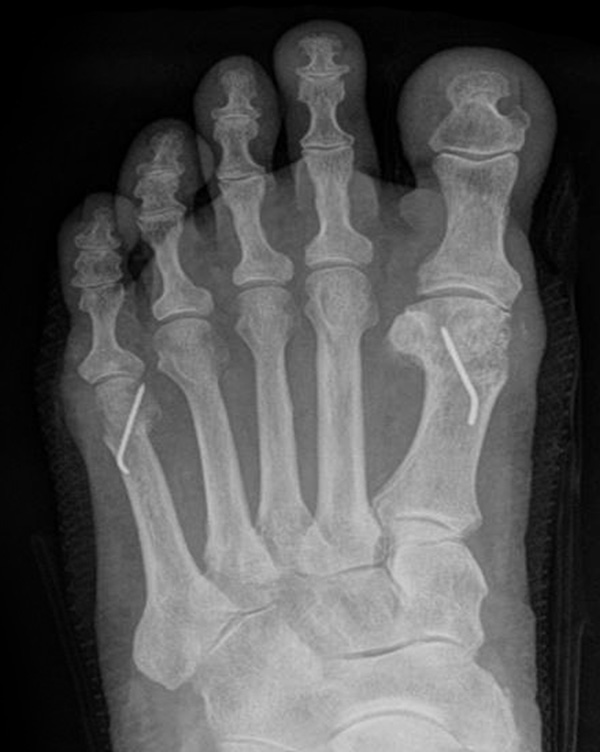

Abb. 8 a, b, c: Typ III Deformität mit prä- (a) und postoperativem Röntgenbild (b, c) mit Schrauben-Osteosynthese.

Abb. 9 a, b: Typ III Deformität mit prä- (a) und postoperativem Röntgenbild (b).